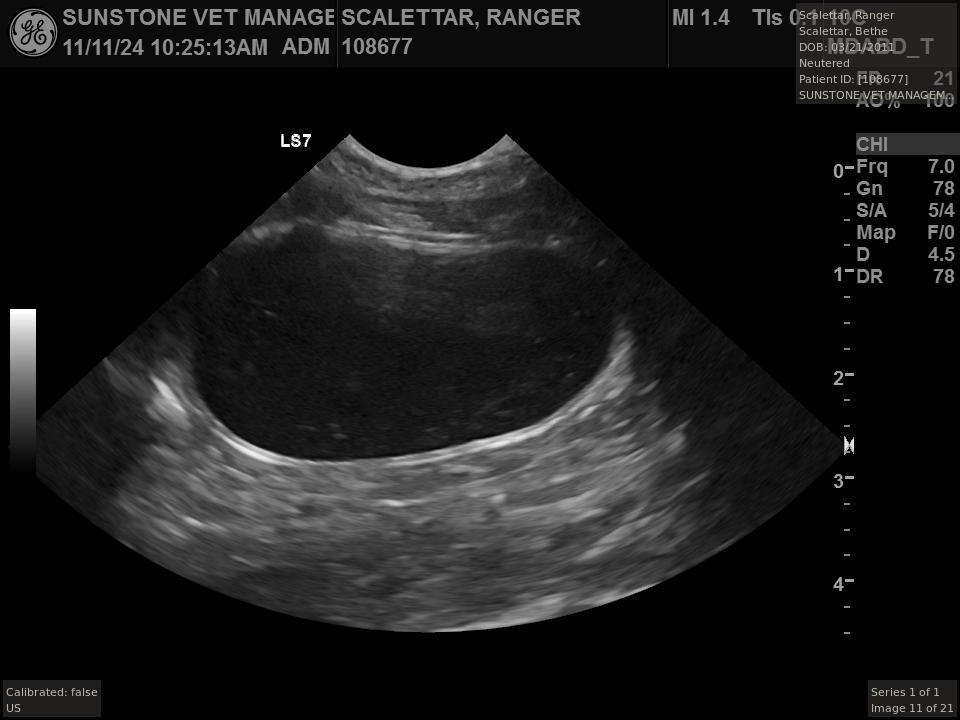

Veterinary ultrasound examinations of the thorax and/or abdomen typically include a number

of views selected to assess the health and function of internal organs. Unlike with radiography,

the images do not include the lungs because ultrasound reflects off the outer boundaries of the

lungs, making it difficult to see inner structures.

The veterinarian generated a series of images showing different organs and substructures by

changing the position and orientation of the ultrasound transducer. The images were collected

in a defined order, which is repeated from patient to patient, ensuring that nothing is missed. In

Ranger's case, the sonographer collected about twenty images during an examination that

lasted about fifteen minutes.

The sonographer stated that Ranger's ultrasound images were largely normal for an older cat. In particular, they show changes in the kidneys that are commonly noted in geriatric cats and that reflect a risk for the development of chronic kidney disease. However, the images did not show any significant abnormalities in Ranger's stomach, intestines, and associated lymph nodes. Nonetheless, the results did not rule out recurrence of Ranger's small cell lymphoma.